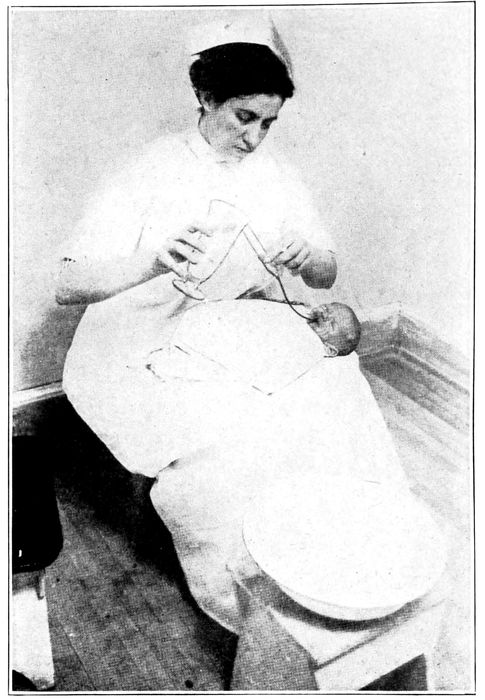

| 121. |

Method of giving gavage |

284 |

| |